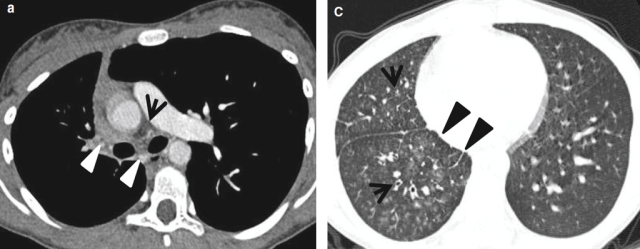

右肺动脉近端中断是一种罕见的发育异常,所谓“中断”更常见于肺动脉缺如,通常与其他先天性心脏畸形有关,如室间隔缺损、法洛四联征、主动脉缩窄、主动脉瓣狭窄、大血管转位、弯刀综合征和主-肺动脉瘘。

例如,以下是一例右肺动脉近端中断的10岁女孩。胸部增强CT扫描(主支气管水平,纵隔窗,左图)可见右肺动脉近端在心包内中断(黑箭头),且右支气管动脉及其分支增粗(白箭头)。肺窗(心室水平,右图)可见由扩张的支气管和伴随的支气管小动脉构成的印戒征,伴小叶中心毛玻璃密度结节(细箭头),右肺可见小叶间隔增厚(粗箭头)[7]。

右肺动脉近端中断的10岁女孩的胸部增强CT(左:纵隔窗;右:肺窗)[7]